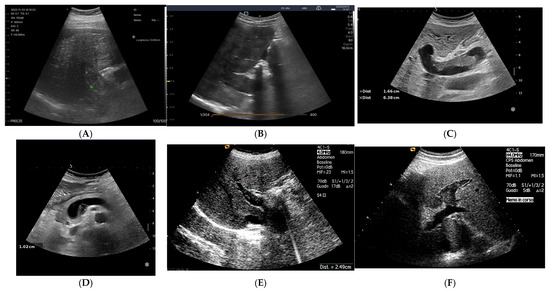

Review

Myocardial Mechanics and Associated Valvular and Vascular Abnormalities in Left Ventricular Noncompaction Cardiomyopathy

by Attila Nemes

Left ventricular (LV) non-compaction (LVNC) is a rare genetic cardiomyopathy due to abnormal intra-uterine arrest of compaction of the myocardial fibers during endomyocardial embryogenesis. Due to the partial or complete absence of LV compaction, the structure of the LV wall shows characteristic abnormalities, [...] Read more.

Left ventricular (LV) non-compaction (LVNC) is a rare genetic cardiomyopathy due to abnormal intra-uterine arrest of compaction of the myocardial fibers during endomyocardial embryogenesis. Due to the partial or complete absence of LV compaction, the structure of the LV wall shows characteristic abnormalities, including a thin compacted epicardium and a thick non-compacted endocardium with prominent trabeculations and deep intertrabecular recesses. LVNC is frequently associated with chronic heart failure, life-threatening ventricular arrhythmias, and systemic embolic events. According to recent findings, in the presence of LVNC, dysfunctional LV proved to be associated with left atrial volumetric and functional abnormalities and consequential dilated and functionally impaired mitral annulus, partly explaining the higher prevalence of regurgitation. Although the non-compaction process morphologically affects only the LV, signs of remodeling of the right heart were also detected. Moreover, dilation and stiffening of the aorta were present. The aim of the present detailed review was to summarize findings regarding changes in cardiac mechanics, valvular abnormalities, and vascular remodeling detected in patients with LVNC. Full article

Show Figures

Figure 1